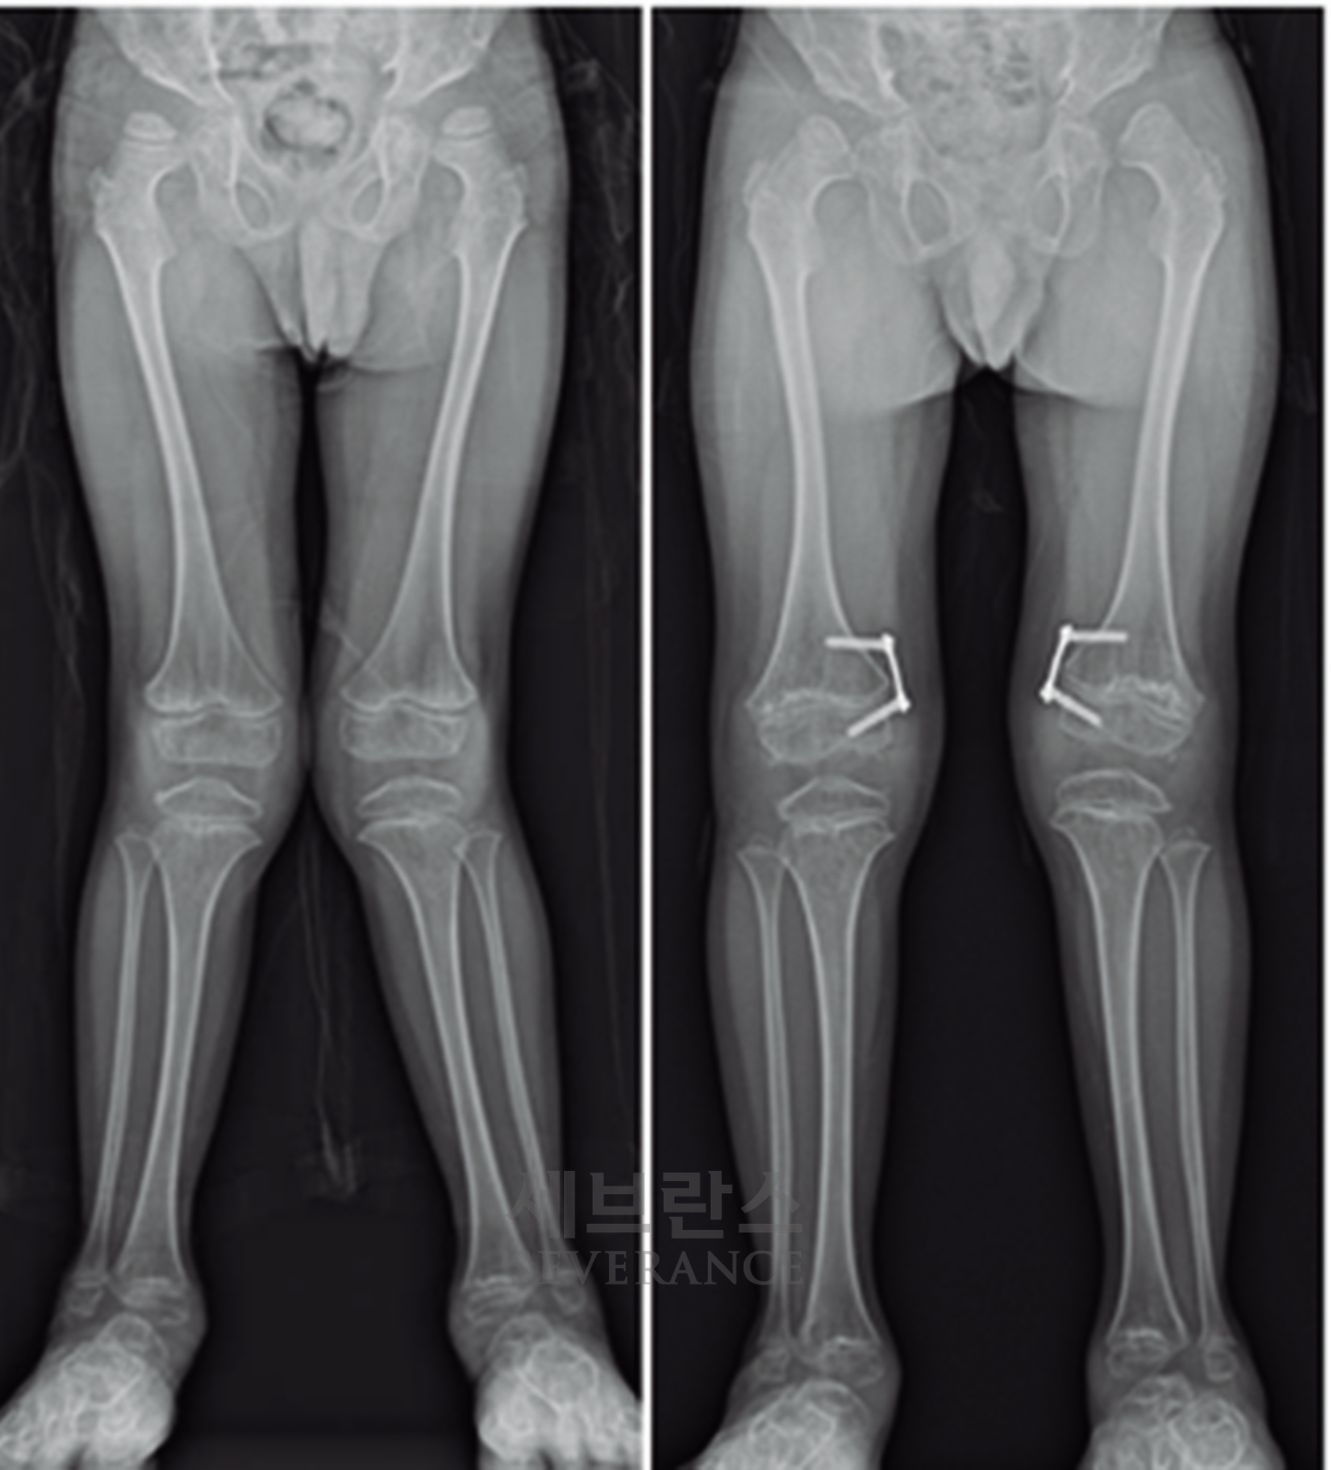

구루병으로 발생한병적 내반슬(O다리) 변형에 대해

절골 교정술을 시행한 환아

성장이 끝난 환자나 변형이 심한 경우에는 절골 교정술이 효과적입니다. 이 수술은 뼈를 잘라 바른 위치로 되돌린 뒤 금속 장치로 고정하는 방식으로, 수술 직후 곧바로 교정 효과를 볼 수 있습니다. 그러나 절골된 뼈가 단단히 붙을 때까지 약 2-3개월이 소요되며, 그동안은 목발 보행 등 활동에 제약이 따릅니다.